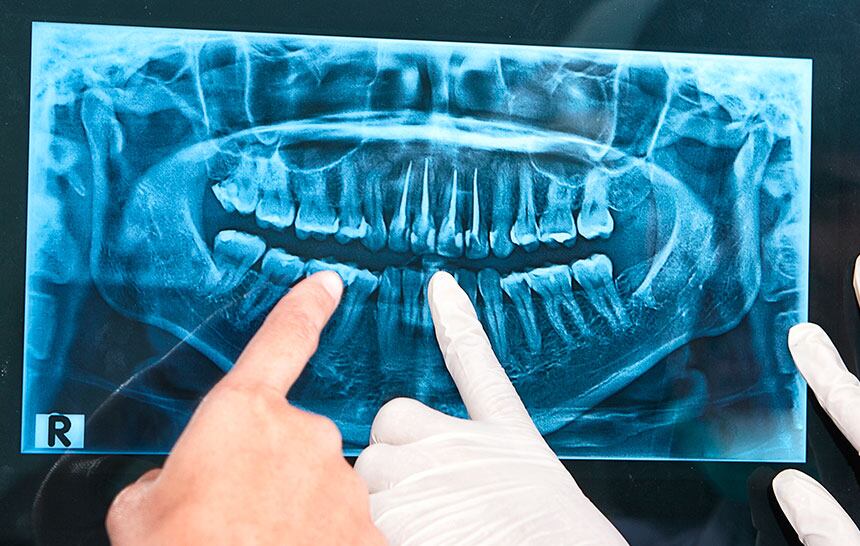

Para ello, este requiere de una radiografía panorámica, recurso que le permitirá trabajar con concisión y con el mínimo margen de error.

Señala la Odontóloga Teruelo De Luis que “una vez que hemos realizado una radiografía panorámica, hago una exploración de la boca y comento con el paciente sobre las patologías existentes, en el caso de haberlas, y de los tratamientos a aplicar de manera totalmente personalizada”.

Así mismo, en el citado sitio web se agrega que “la radiografía panorámica es la prueba diagnóstica más importante dentro de las que se realizan en la primera visita a la clínica dental, por tanto, nos permite observar el estado de los dientes, de los huesos maxilares, articulación temporo-mandibular (ATM), ligamentos, etc, con una gran nitidez. Esto nos ayuda a observar de manera general y completa el estado bucal de nuestros pacientes y, a partir de ahí, diagnosticar y tratar los problemas dentales”.